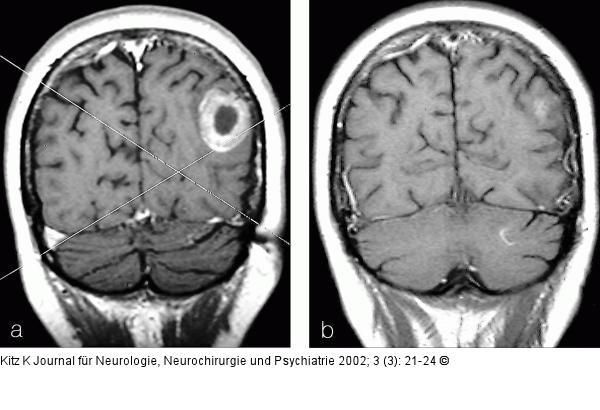

Abbildung 4a-b: Hirnmetastase - Planungs-MRT für Gamma Knife 4a: Hirnmetastase (multipel) bei Adeno-Ca der Lunge, Planungs-MRT (T1 mit KM, 3 mm). 4b: Kontroll-MRT (T1 mit KM) 7 Monate nach Gamma Knife und Ganzhirnbestrahlung. |

Abbildung 4a-b: Hirnmetastase - Planungs-MRT für Gamma Knife

4a: Hirnmetastase (multipel) bei Adeno-Ca der Lunge, Planungs-MRT (T1 mit KM, 3 mm). 4b: Kontroll-MRT (T1 mit KM) 7 Monate nach Gamma Knife und Ganzhirnbestrahlung. |